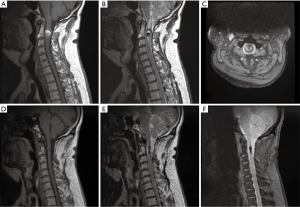

A 56-year-old male presented with sensory changes in his right hand which progressed over a period of weeks to bilateral sensory changes in the upper and lower limbs, gait imbalance, urinary and faecal incontinence and loss of temperature perception. He subsequently developed significant weakness in the upper limbs. Preoperative magnetic resonance imaging (MRI) of the cervical spine (Figure 1) was suggestive of a SCIC and given his rapid neurological decline, a surgical approach to therapy was adopted.

Immediately postoperatively, dense hemiparesis was noted on the right side, however, there was steady improvement in both motor and sensory function over the subsequent days in addition to a complete return of bladder and bowel function. No postoperative complications were noted. Histopathology (Figure 2), consistent with SCICs with hemorrhage, displayed areas of tissue with increased vascularity and characteristic thin walled blood vessels of various sizes. A MRI (Figure 1) was obtained 11 months postoperatively and showed reduced mass effect and resolved spinal cord oedema. The patient continued to demonstrate slow but steady improvement at all postoperative follow-ups.